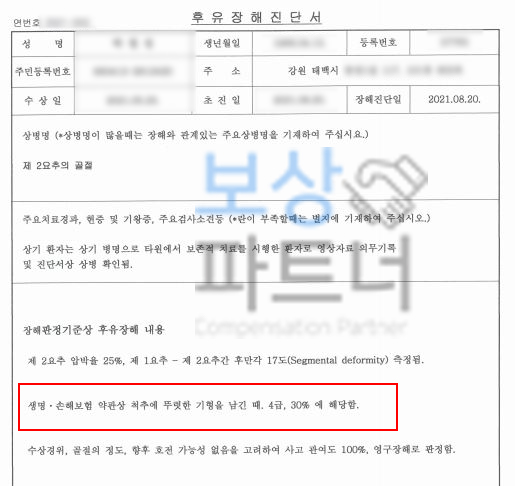

소개해드릴 박@@님은 강원 태백시 거주하시는 50대 여성분이셨습니다. 자택에서 스트레칭을 하시던 중 의자에서 넘어지셨는데요, 위 단순한 사고로 허리에 극심한 통증을 호소하셨고 병원에 내원하여 정밀검사 받아보니..

제2번 요추압박골절 S32030 진단받아 허리 보조기 착용하는 보존적 치료 시행해야 했습니다. 최소 8주간 안정을 취해야 하셨는데요, 가정에서 주부이시기도 했지만 일을 하시기도 하셨기 때문에

저희는 의뢰인과 충분한 소통 후, 장해를 평가할 수 있는 적정한 시점에 객관적이고 공정한 평가를 받을 수 있도록 제3의 공신력있는 대학병원의 전문의로부터 요추2번의 후유장해 평가 진행하였습니다.

그 결과,

생명, 손해보험 약관상 뚜렷한 기형 30% 지급률 급수 보험으로는 4급에 해당하는 척추의 장해에 해당하셨고, 기왕증의 요인 없이 사고관여도 100% 영구장해 평가 받으셨습니다. 아무리 공신력있는 대학병원의 후유장해 평가를 받았다고 해도